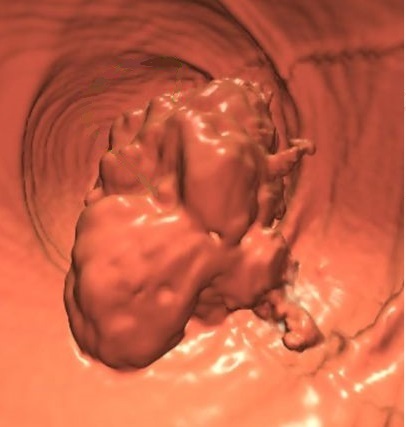

Aspect macroscopique du colonoscopie , sigmoidoscopie

et coloscopie virtuelle d'une adenome carcionoma du colon .

Aspect macroscopique de

coloscopie d'une adenocarcinoma du colon |

Aspect d'une

autre cas de adenome carcinoma du colon . Image

macroscopique d'une sigmoidoscopie |